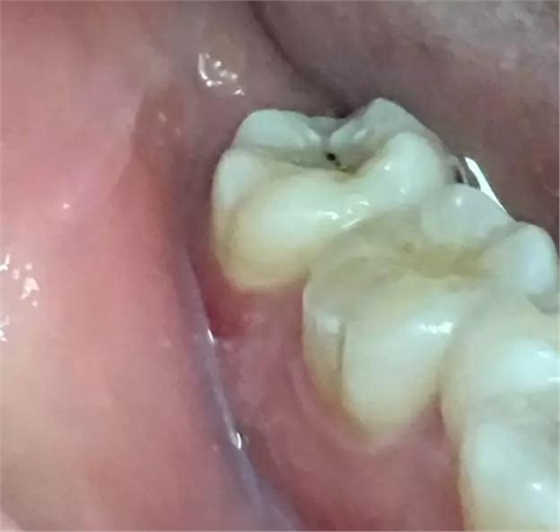

圖2. 37牙冠基本完好,松動Ⅰ度。合面有一開髓孔被棉球覆蓋,頰側(cè)牙齦輕度紅腫。

圖3. 取出棉球口內(nèi)發(fā)現(xiàn)37合面有開髓孔,探針出血,頰側(cè)牙齦紅腫。